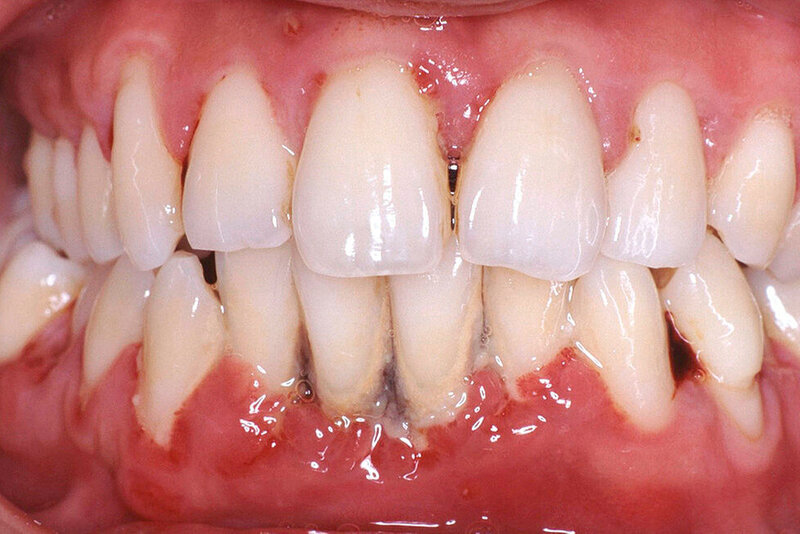

Mukogingivale Zustände

Die Bedeutung des Gingiva-Phänotyps – einschließlich der Gingivadicke und -breite – wird jetzt anerkannt und eine neue Klassifikation für gingivale Rezessionen ist eingeführt worden. Dabei werden klinische Parameter wie der gingivale Phänotyp, der interproximale Attachmentverlust und die Charakteristika der freiliegenden Wurzeloberfläche kombiniert.

Mukogingivale Zustände werden nach gingivalem Phänotyp, interproximalem Attachmentverlust und den Charakteristika der exponierten Wurzeloberfläche klassifiziert.